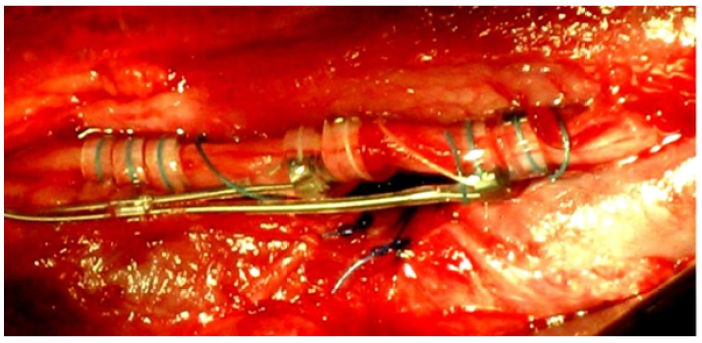

The Benefit of Vagus Nerve Stimulation in Patients with Refractory Epilepsy, Experience in a Latin American Center

Manuel Hernandez Salazar, Ramos Delgado Jose Miguel and Aguilar Trujillo Annette Aime. 15(4): 01-16.